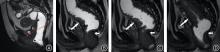

目的 回顾性总结分析孤立性直肠溃疡综合征(SRUS)患者的X线排粪造影(XRD)和MR排粪造影(MRD)的影像学表现,为临床诊疗提供重要信息。 方法 19例经临床、病理和肠镜检查证实的SRUS患者纳入本研究,15例行XRD,7例行MRD,3例患者同时进行了XRD和MRD检查。收集所有患者的数据并进行盆底功能测量。 结果 在XRD结果中,3例(20%)表现直肠内套叠,8例(53.3%)直肠外脱垂,2例(13.3%)中度直肠前突。另外耻骨直肠肌肥厚患者有2例,膀胱脱垂和子宫脱垂患者各有1例。在MRD结果中,3例(42.9%)表现直肠黏膜脱垂(部分性脱垂),4例(57.1%)直肠前突患者中,3例(均为女性)为中度直肠前突,1例为轻度直肠前突。3例患者同时观察到相关的前、中腔室器官下降,2例耻骨直肠肌肥厚,没有患者表现乙状结肠疝。 结论 排粪造影可以评估SRUS患者的直肠外脱垂、直肠前突、直肠黏膜脱垂、直肠内套叠等盆底结构及功能异常,对SRUS患者的治疗具有指导意义。

Objective The imaging findings of X?ray defecography (XRD) and magnetic resonance defecography (MRD) of patients with Solitary Rectal Ulcer syndrome (SRUS) were retrospectively analyzed to provide important information for clinical diagnosis and treatment. Methods 19 patients with SRUS confirmed by clinical, pathological and colonoscopy were included in this study. Among them, 15 patients underwent XRD and 7 patients underwent MRD, and 3 patients underwent both XRD and MRD. Data of all enrolled patients were collected and pelvic floor function was measured. Results In the results of XRD, 3 patients (20%) showed rectal intussusception. 8 patients (53.3%) showed external rectal prolapse and 2 patients (13.3%) showed moderate rectocele. In addition, there were 2 patients of puborectal muscle hypertrophy, and 1 patient of bladder prolapse and uterine prolapse, respectively. For MRD, 3 patients (42.9%) showed rectal mucosal prolapse (partial prolapse). At 4 patients (57.1%) with rectocele, 3 patients (all female) had moderate rectocele, 1 patient had mild rectocele. 3 patients were also observed related anterior and middle compartment organ descent. 2 patients of pubulorectal muscle hypertrophy, no sigmoidocoele. Conclusion Defecography can evaluate the structural and functional abnormalities of pelvic floor in SRUS patients, such as external rectal prolapse, rectal protrusion, rectal mucosal prolapse, and rectal intussusception, which has guiding significance for the treatment of SRUS patients。